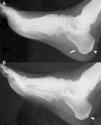

El estudio radiológico de manos, pies, tobillos y rodillas solo mostraba aumento de partes blandas en las localizaciones correspondientes a artritis, sin erosiones ni pinzamientos articulares, pero se identificaron entesofitos aquíleos bilaterales y espolón calcáneo derecho (fig. 2). La radiografía y la resonancia magnética de sacroiliacas fueron normales. En la ultrasonografía-Doppler se detectaron signos de sinovitis en segunda IFP y tenosinovitis de tendón flexor del tercer dedo de la mano izquierda, metatarsofalángica segunda y tercera derechas y segunda izquierda, articulación tibioastragalina izquierda y rodilla derecha, sin aumento de señal power-Doppler.